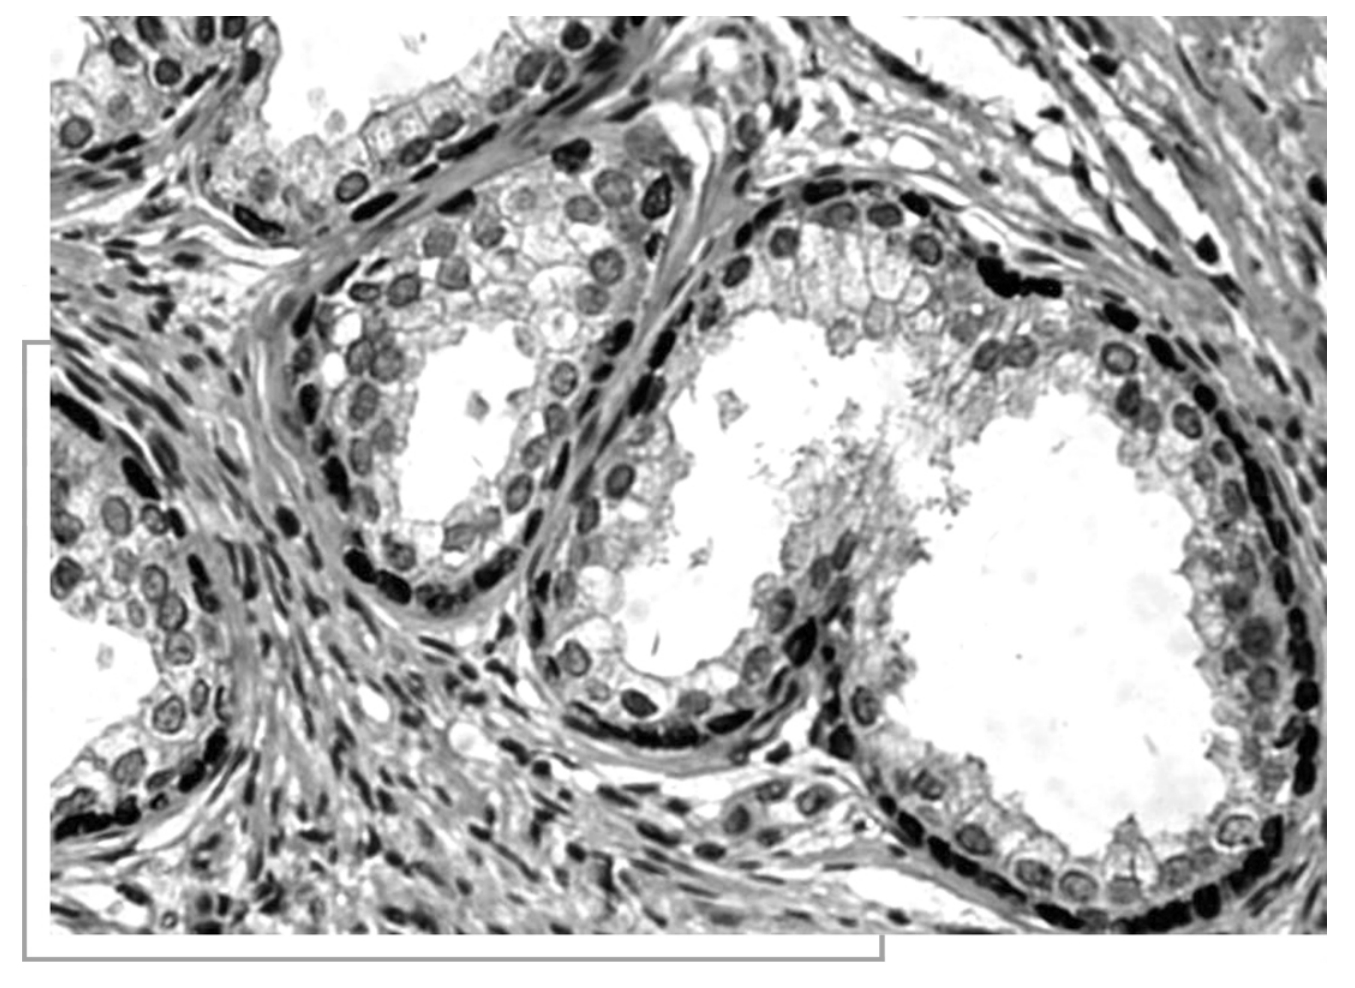

鼠单克隆抗体(https://www.daowen.com)